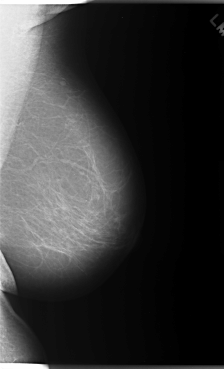

C_0086_1.LEFT_MLO

LEFT_MLO LINES 5896 PIXELS_PER_LINE 3576 BITS_PER_PIXEL 12 RESOLUTION 50 NON_OVERLAY

FILE: C_0086_1.RIGHT_CC.OVERLAY

TOTAL_ABNORMALITIES 1

ABNORMALITY 1

LESION_TYPE MASS SHAPE LOBULATED MARGINS MICROLOBULATED

ASSESSMENT 5

SUBTLETY 5

PATHOLOGY MALIGNANT

TOTAL_OUTLINES 1

BOUNDARY